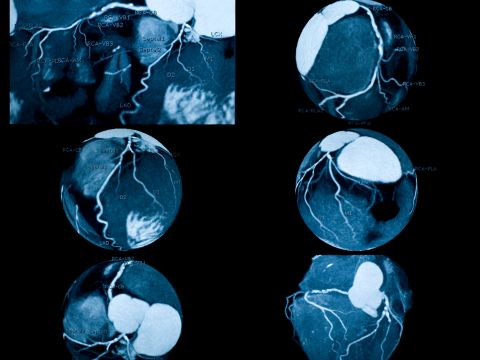

It captures crystal-clear images of your coronary vessels — detecting blockages, plaque buildup, or narrowing that could lead to a heart attack, often before you feel a single symptom.

This scan clearly visualizes:

Coronary Arteries Plaque Deposits Calcium Scoring Vessel Narrowing Heart Chambers Aorta